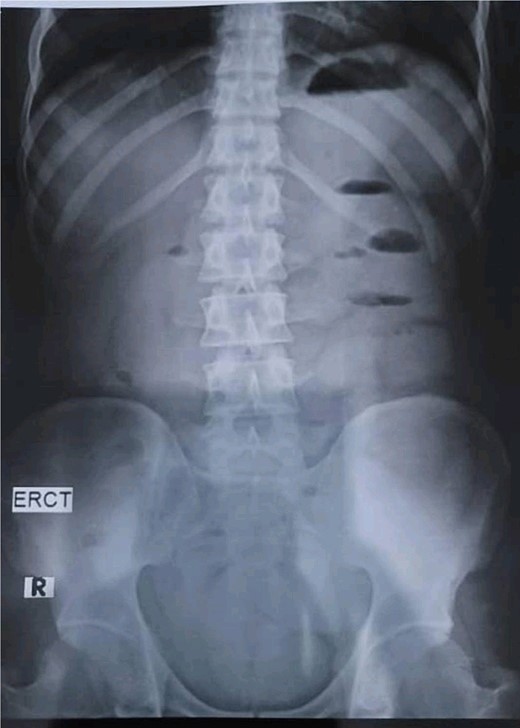

A 28-year-old female patient arrived at the emergency department complaining of intermittent colicky abdominal pain and presenting with tachycardia. She had not passed stool or flatus for 3 days, accompanied by vomiting. Upon physical examination, mucocutaneous hyperpigmentation was observed in the oral cavity (Fig. 1), along with a distended abdomen and increased bowel movement, which were hypertympanic on percussion. Initial investigations, including abdominal and pelvic ultrasonography, abdominal X-rays in erect and supine positions (Fig. 2), chest X-ray and computed tomography scan, revealed a 3-cm diameter, a 5 air level fluid, a U-shaped distension with 3.2-cm diameter mural thickening, mesenteric fat infiltration, and pneumatosis. There were no signs of peritonitis, and laboratory values fell within normal limits.

Abdominal X-rays in erect position reveals five air fluid levels.